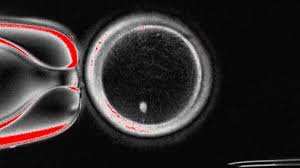

Щоб створити яйцеклітину, науковці використовували ядра з клітин шкіри – вони містять значну частину генетичної інформації. Згодом їх пересаджували в донорську яйцеклітину, в якій не було власного ядра.

Загалом вчені створили 82 функціональні ооцити – незрілі яйцеклітини, які згодом запліднили в лабораторних умовах.

Найбільшим викликом дослідників було переконатися, що запліднена яйцеклітина має правильну кількість хромосом.

Для цього вони розробили метод видалення зайвих хромосом, який імітував природний поділ клітин.

Попри ці досягнення менше ніж 9% яйцеклітин дожили до стадії, яка відповідає п’ятому-шостому дню після запліднення. У випадку ЕКО в цей час ембріони зазвичай переносять у матку.